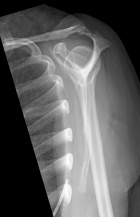

37 year old AAF with four months of right shoulder pain

Zoom image: Radiological image Radiological image.